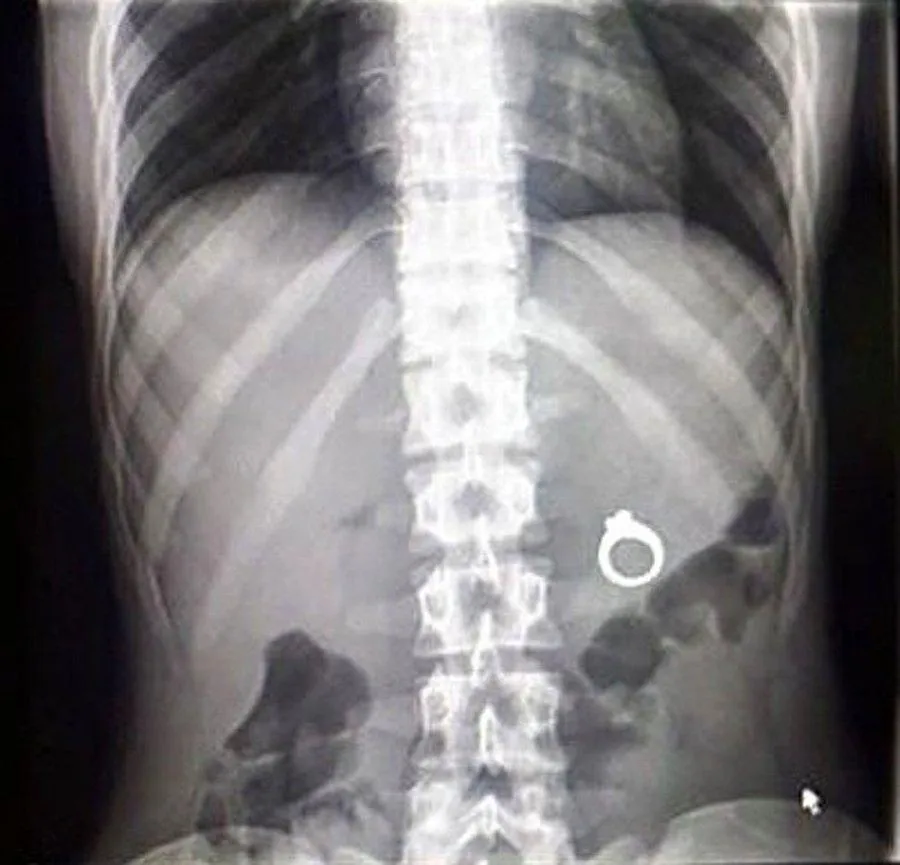

Ничего особенного. Просто кто-то проглотил… снежинку

Фото onedio